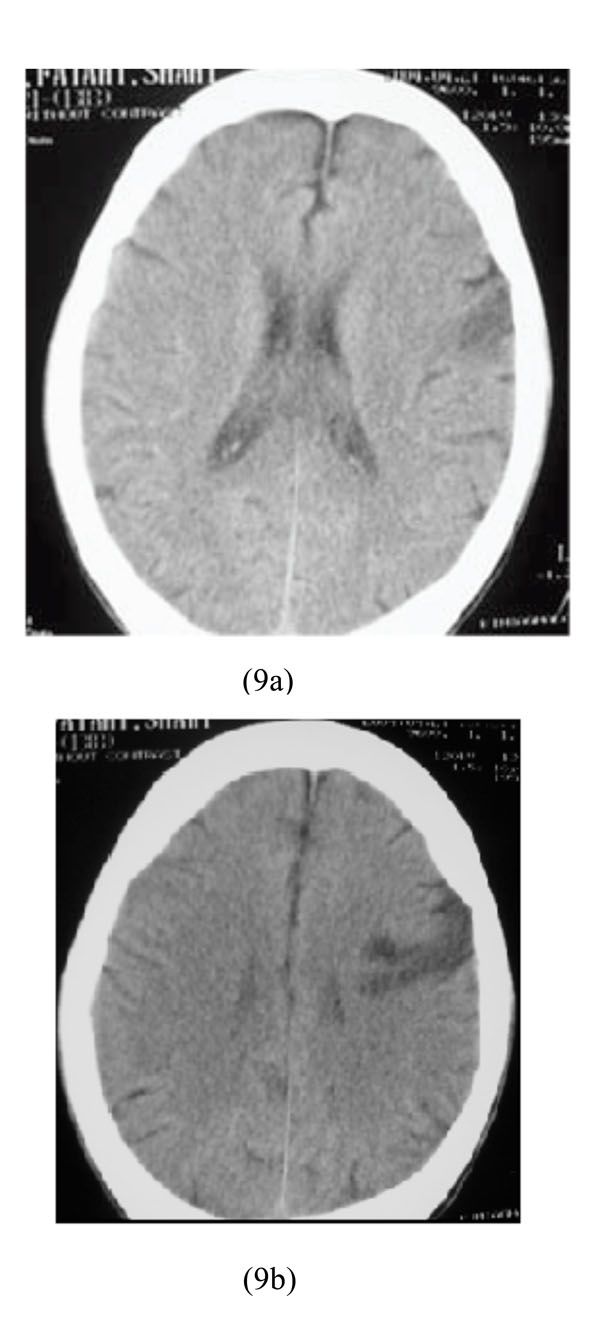

A 32-year-old heroin abuser man was hospitalized due to non-cardiogenic pulmonary edema and right hemiparesia as a result of heroin intoxication. Physical examination showed: BP=90/60, PR=90/min, RR=12/min and right hemiparesia. He underwent brain CT scan which revealed left frontal lobe infarction (Figs. 9a-9b).

Left frontal lobe infarction in heroin intoxication.